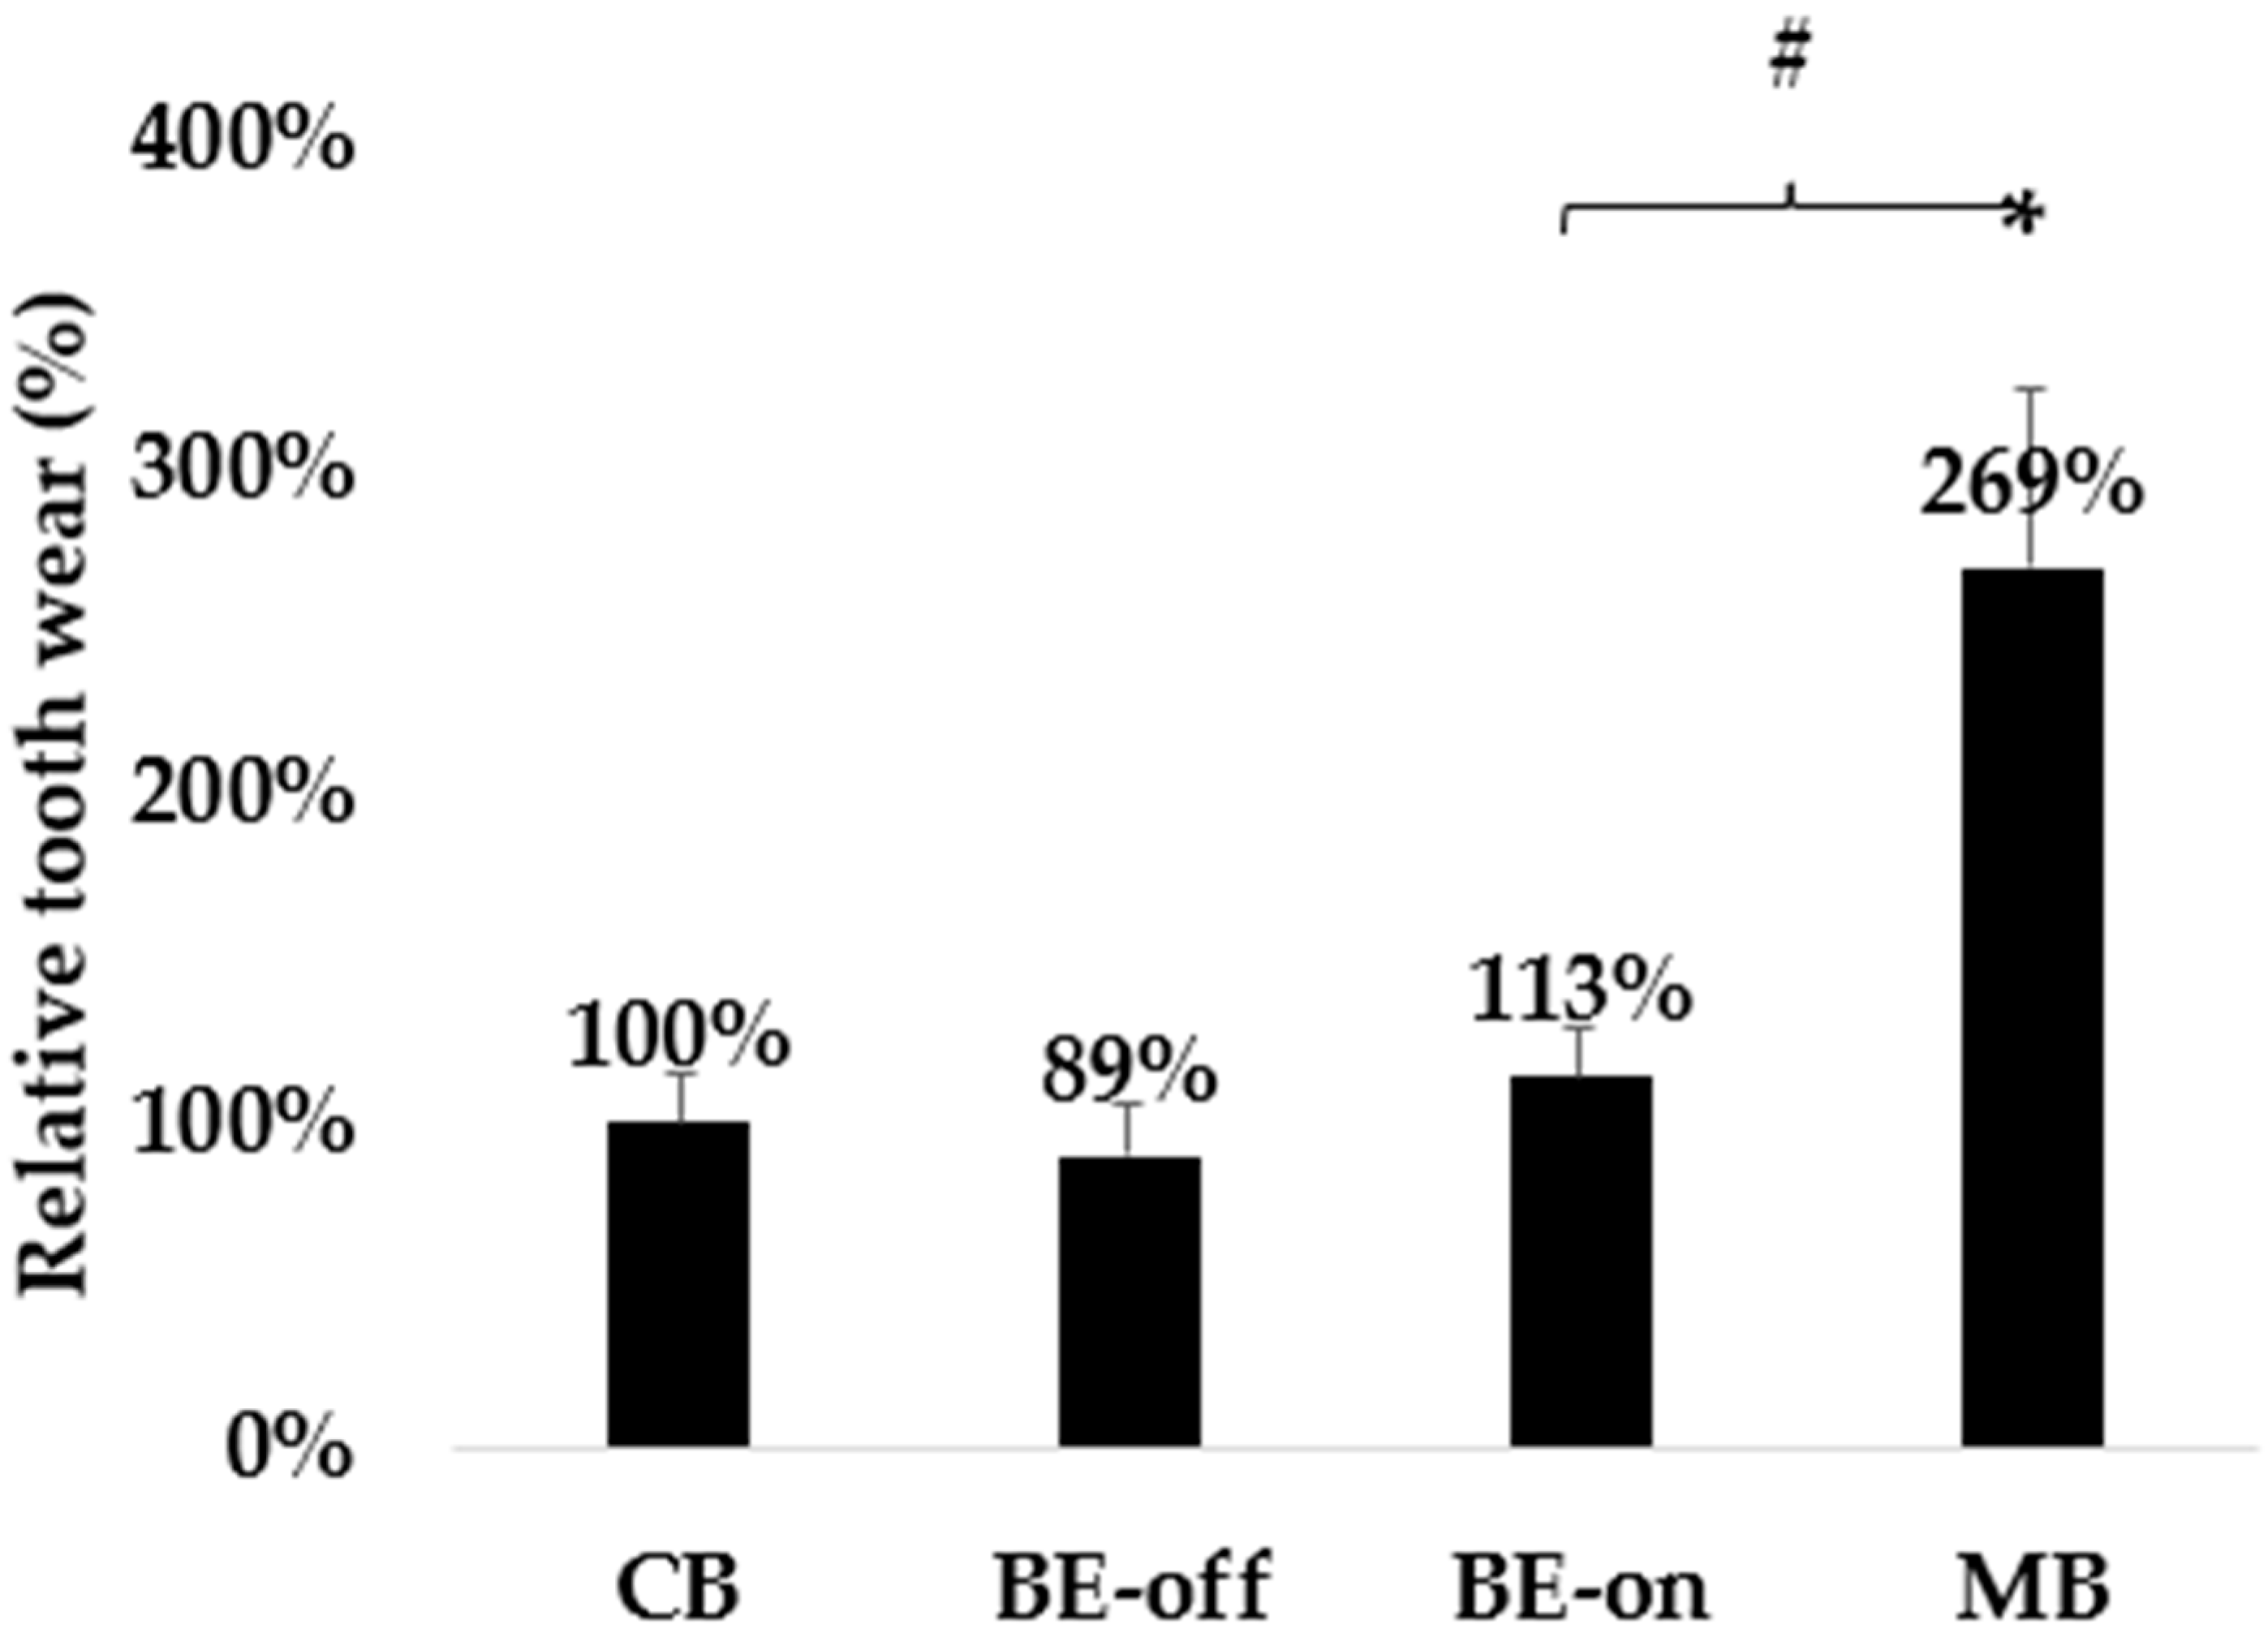

3.2. Experiment with Wear

| Conditions of the Toothbrush | Changes of the PMMA before and after the Surface Friction Wear Experiment (N = 5, Each Condition) |

|---|---|

| CB | 7.46 ± 1.12 μm |

| BE-off | 6.41 ± 1.23 μm |

| BE-on | 8.33 ± 1.18 μm |

| MB | 20.25 ± 4.02 *,# μm |